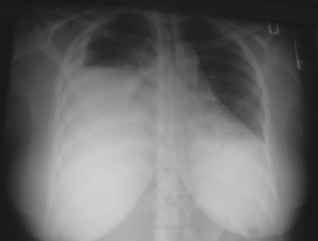

<p>For 4 days, a 34-year-old preg- nant woman had dyspnea and right-sided chest pain. She denied fever, chills, sweats, cough, lower extremity pain,and edema. Surgical and social histories were...